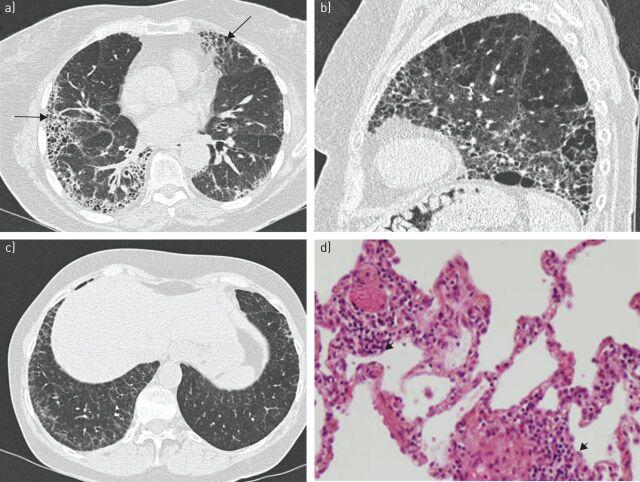

In 9-20% of cases, Sjögren's syndrome is associated with various respiratory symptoms. The most typical manifestations are chronic interstitial lung disease (ILD) and tracheobronchial disease. The most common manifestation of ILD is nonspecific interstitial pneumonia in its fibrosing variant. Other types of ILD, such as organising pneumonia, usual interstitial pneumonia and lymphocytic interstitial pneumonitis, are rare. Their radiological presentation is less distinctive, and definitive diagnosis may require the use of transbronchial or surgical lung biopsy. Corticosteroid therapy is the mainstay of ILD treatment in Sjögren's syndrome, but the use of other immunosuppressive drugs needs to be determined. ILD is a significant cause of death in Sjögren's syndrome. Tracheobronchial disease is common in Sjögren's syndrome, characterised by diffuse lymphocytic infiltration of the airway. It is sometimes responsible for a crippling chronic cough. It can also present in the form of bronchial hyperresponsiveness, bronchiectasis, bronchiolitis or recurrent respiratory infections. The management of these manifestations may require treatment for dryness and/or inflammation of the airways. Airway disease has little effect on respiratory function and is rarely the cause of death in Sjögren's syndrome patients. Rare respiratory complications such as amyloidosis, lymphoma or pulmonary hypertension should not be disregarded in Sjögren's syndrome patients.

在9%至20%的病例中,干燥综合征与多种呼吸道症状相关。最典型的表现是慢性间质性肺疾病(ILD)和气管支气管疾病。ILD最常见的表现是纤维化型非特异性间质性肺炎。其他类型的ILD,如机化性肺炎、寻常型间质性肺炎和淋巴细胞间质性肺炎则较为罕见。它们的影像学表现不太具有特征性,明确诊断可能需要进行经支气管或外科肺活检。糖皮质激素治疗是干燥综合征中ILD治疗的主要手段,但其他免疫抑制药物的使用需要确定。ILD是干燥综合征患者死亡的重要原因。气管支气管疾病在干燥综合征中很常见,其特征是气道弥漫性淋巴细胞浸润。它有时会导致严重的慢性咳嗽。它也可能表现为支气管高反应性、支气管扩张、细支气管炎或反复呼吸道感染。这些表现的管理可能需要对气道干燥和/或炎症进行治疗。气道疾病对呼吸功能影响较小,很少是干燥综合征患者死亡的原因。干燥综合征患者不应忽视罕见的呼吸道并发症,如淀粉样变性、淋巴瘤或肺动脉高压。